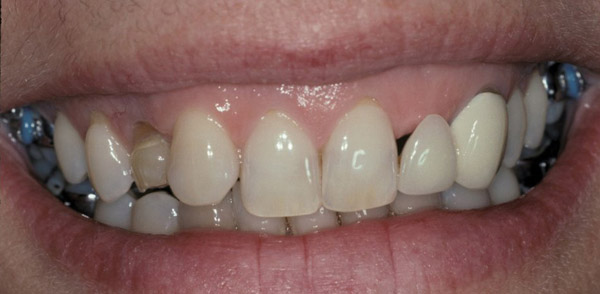

Figure 19  The post-implantation and post-restoration view shows esthetically pleasing, symmetric crowns and mucosal contours, with the Nos. 7 and 10 implant prostheses blending in imperceptibly with the natural dentition. Restoration courtesy of Dr. Jeffrey Warren.

Figure 19